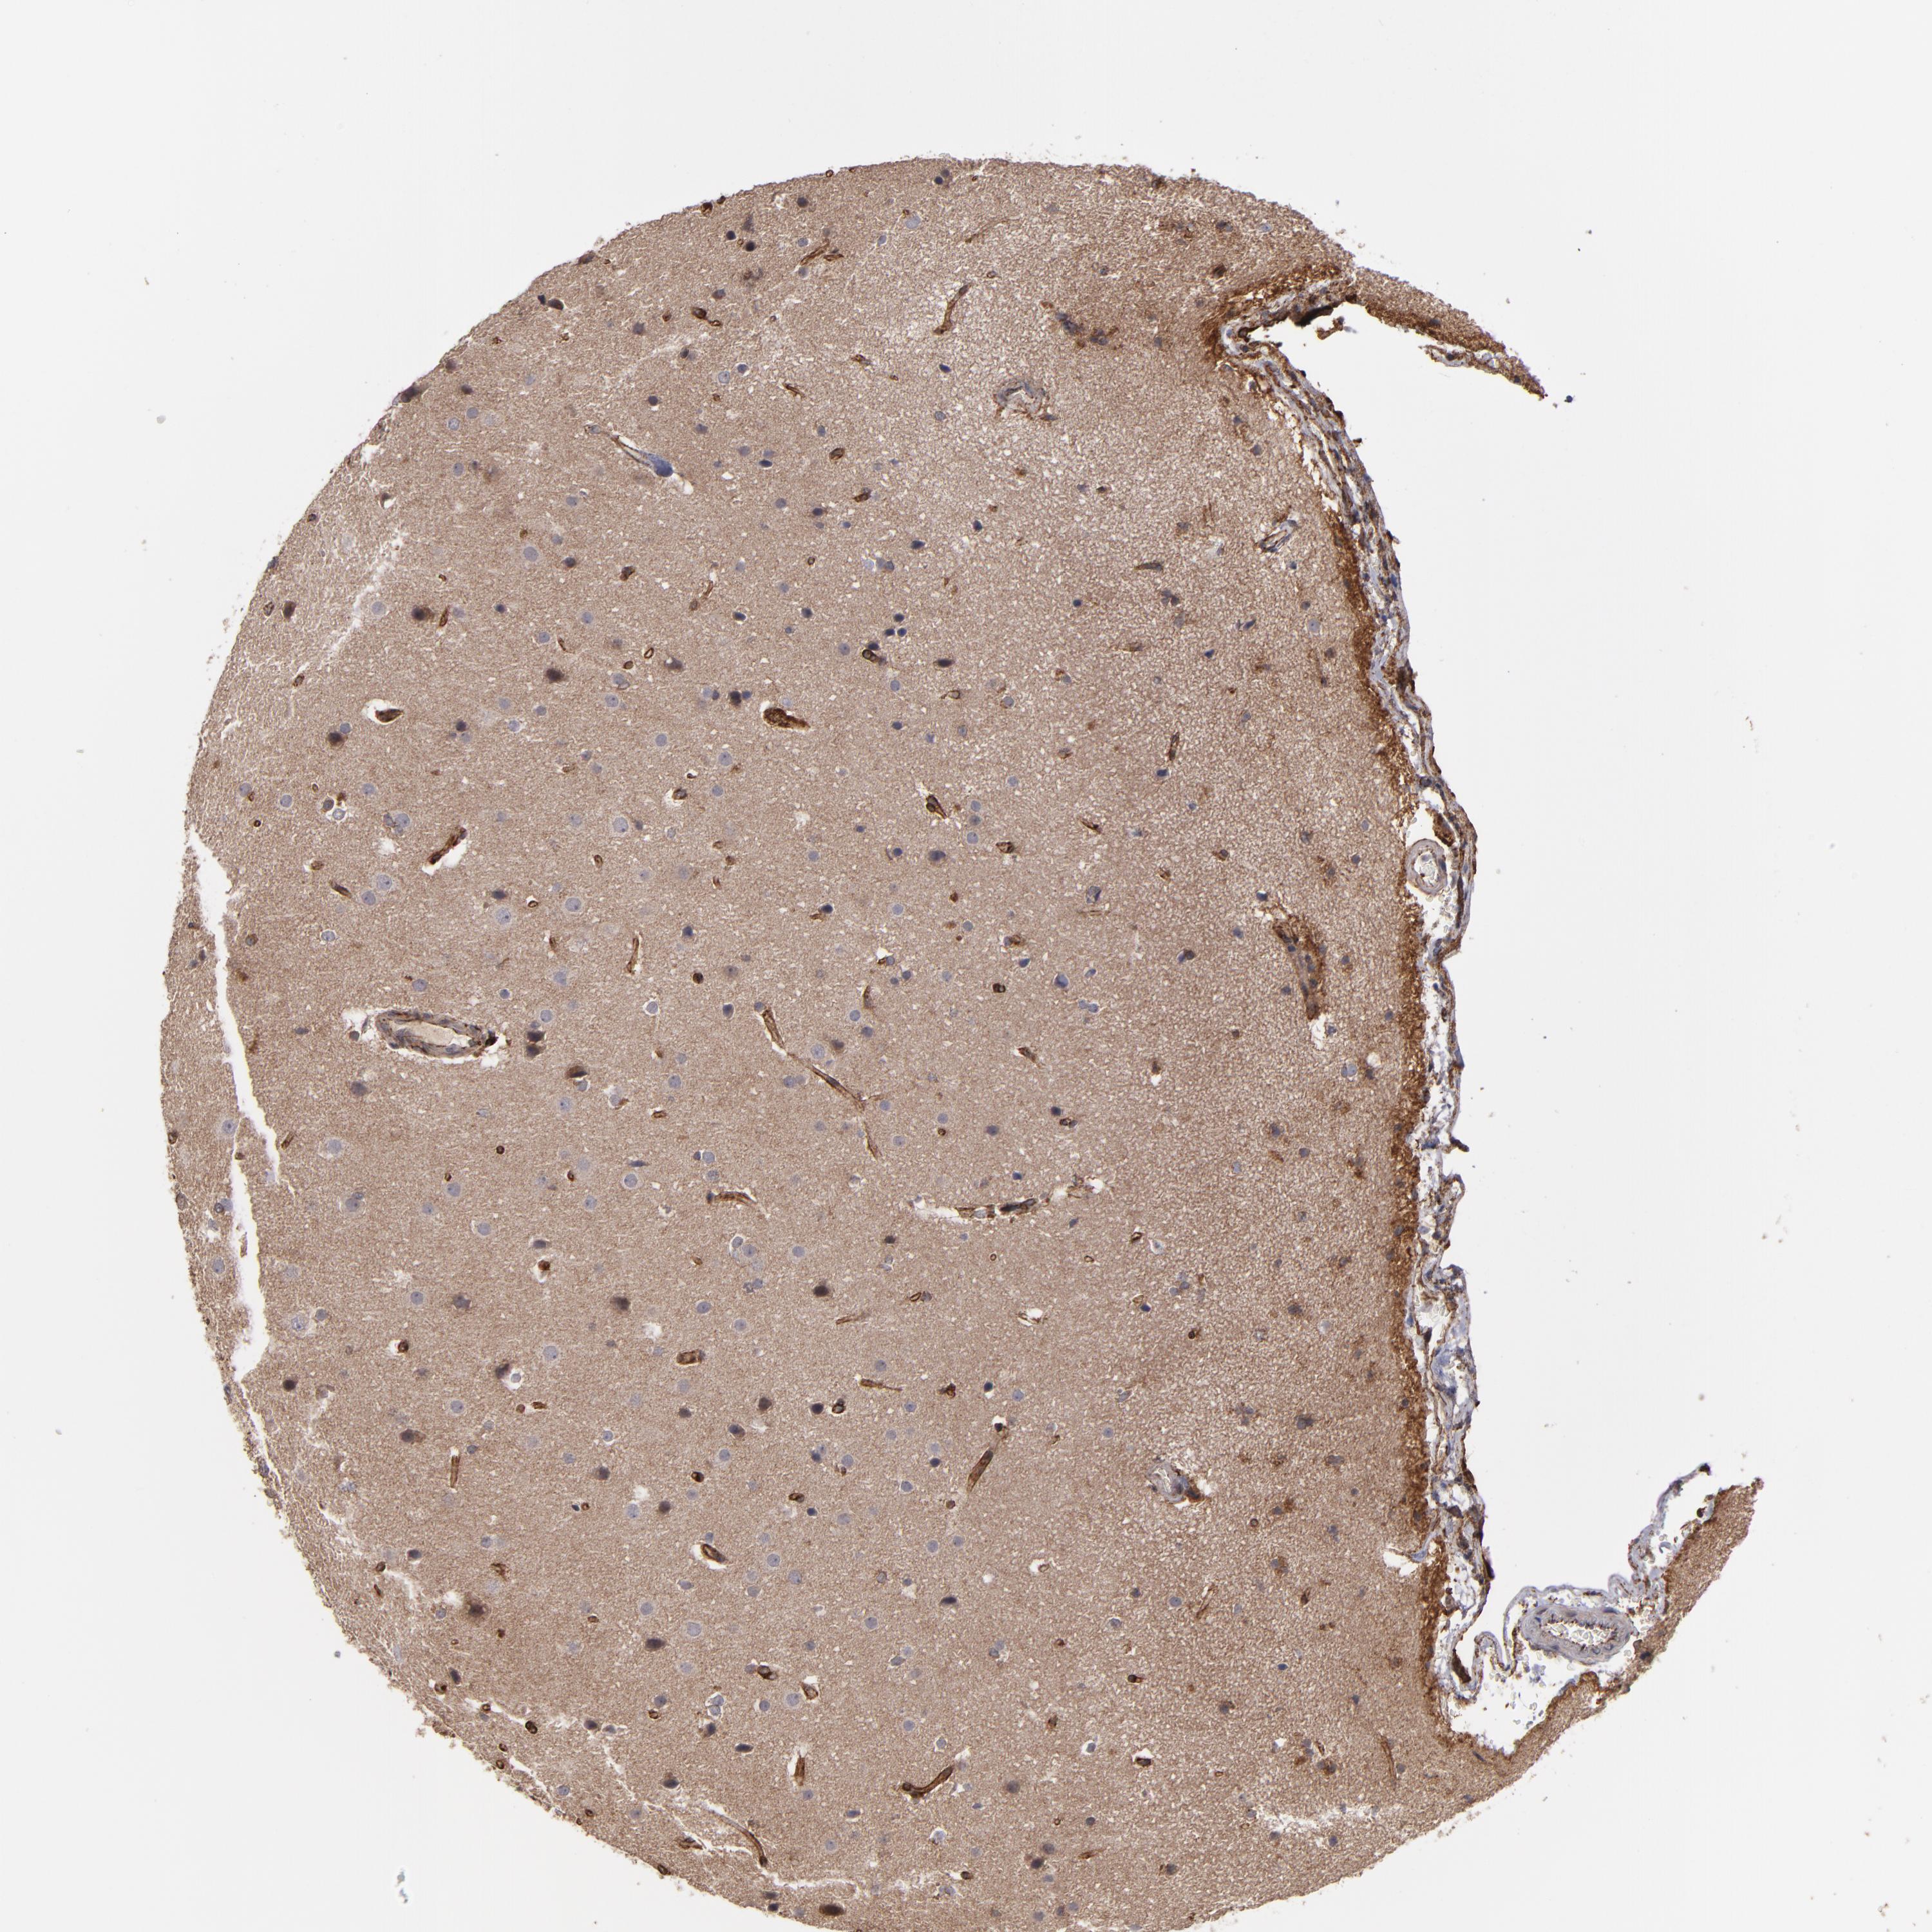

GLIOMA - Protein expressioni

A mouse-over function shows sample information and annotation data. Click on an image to view it in a full screen mode. Samples can be filtered based on level of antibody staining by selecting one or several of the following categories: high, medium, low and not detected. The assay and annotation is described here.

Note that samples used for immunohistochemistry by the Human Protein Atlas do not correspond to samples in the TCGA dataset.

Antibody stainingi

Antibody staining in the annotated cell types in the current human tissue is reported as not detected, low, medium, or high, based on conventional immunohistochemistry profiling in selected tissues. This score is based on the combination of the staining intensity and fraction of stained cells.

Each image is clickable and will lead to virtual microscopy that enables deeper exploration of all samples and also displays staining intensity scores, fraction scores and subcellular localization as well as patient and tissue information for each sample.

Antibody HPA001636

Antibody HPA001637

Antibody CAB010822

Staining

High

Medium

Low

Not detected

Intensity

Strong

Moderate

Weak

Negative

Quantity

>75%

75%-25%

<25%

None

Location

Nuclear

Cytoplasmic/membranous

Cytoplasmic/membranous,nuclear

Glioma, malignant, High grade

Glioma, malignant, Low grade

Glioma, malignant, NOS